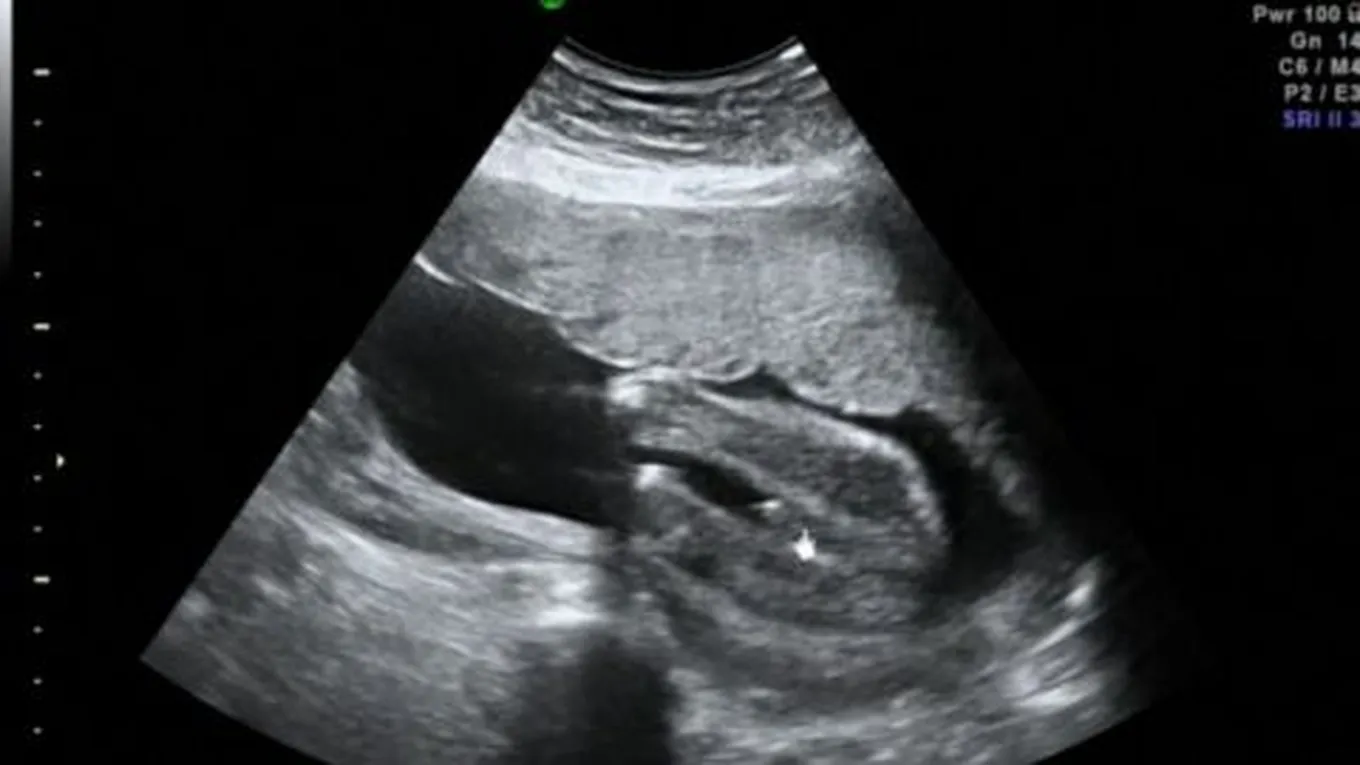

فحص السونارعادة ما يُستخدم فحص السونار أو التصوير بالموجات الصوتيّة (بالإنجليزيّة: Fetal Ultrasound) خلال فترة الحمل بهدف تصوير الجنين داخل الرحم

فحص السونار

عادة ما يُستخدم فحص السونار أو التصوير بالموجات الصوتيّة (بالإنجليزيّة: Fetal Ultrasound) خلال فترة الحمل بهدف تصوير الجنين داخل الرحم (بالإنجليزيّة: Uterus)؛ حيثُ يتم من خلاله تقييم قلب الجنين، ورأسه، وعموده الفقري، وغيرها من أعضاء جسم الجنين، ويعتمد جهاز السونار في عمله على الموجات الصوتيّة المُطلقة عن طريق جهاز إلكتروني يُدعى بمُحوّل الطاقة (بالإنجليزيّة: Transducer)، ومن خلال انتقال الموجات الصوتيّة عبر طبقات الجلد، والعضلات، والسوائل، والعظام، ومن ثمّ انعكاسها؛ تنتج صورة إلكترونيّة للجنين على الجهاز، ويتم تطبيق مادة هُلاميّة على البطن عند إجراء الفحص بهدف تعزيز انتقال الموجات الصوتيّة وتسهيل حركة الجهاز على سطح البطن، وتجدر الإشارة إلى أنّ فحص السونار يُعدّ من الفحوصات الآمنة لتقييم الحمل؛ وذلك لعدم استخدام أي موجات إشعاعيّة خلال إجراء الفحص سواء كان عبر التصوير بالموجات الصوتيّة عن طريق المهبل (بالإنجليزيّة: Transvaginal Ultrasound)، أو التصوير بالموجات الصوتيّة عبر البطن (بالإنجليزيّة: Transabdominal Ultrasound).[1][2]